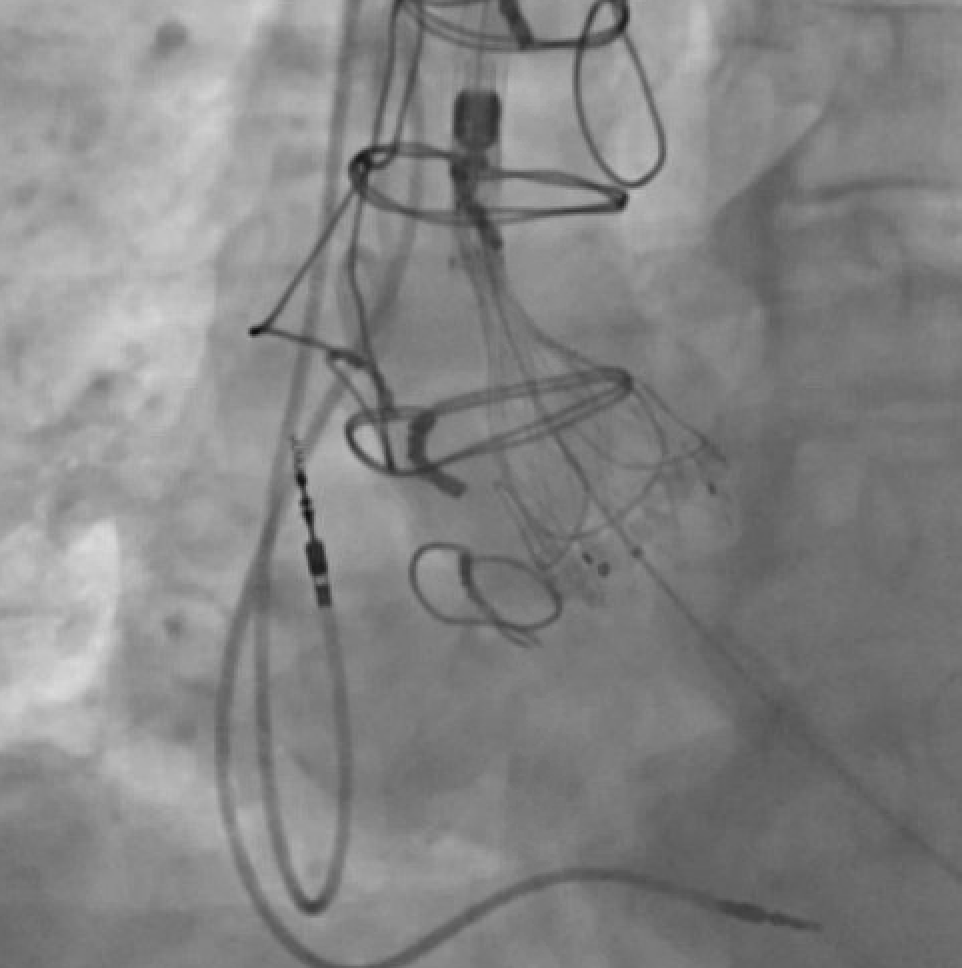

As some have identified, this valve was in-folded. We successfully retrieved the valve and put in a new one. I want to expand on this issue a bit. 🧵

Would you release this 34 mm Evolut? Why or why not? @GuiAttizzaniMD @djc795 @akcmahi